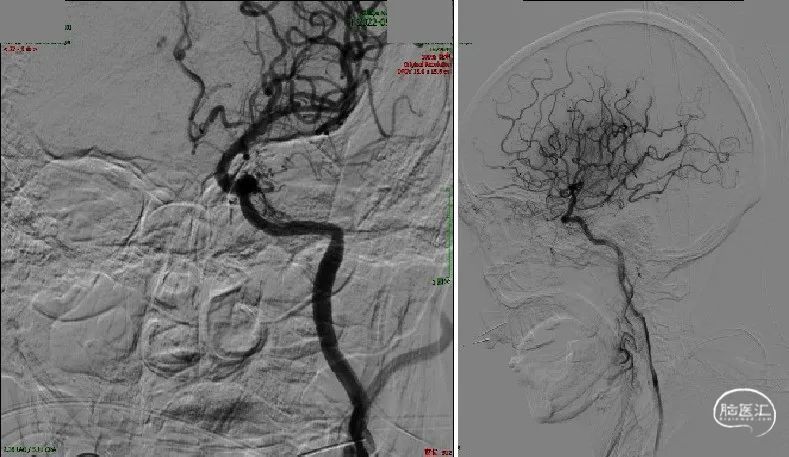

双重负压抽吸下回撤取栓支架,造影见mTICI 3级再通。

保留微导丝,长鞘撤回颈总动脉,将远端保护装置放于岩段,置入7×40mm颈动脉支架。

支架释放,取栓支架及ACE 60内可见多量血栓。